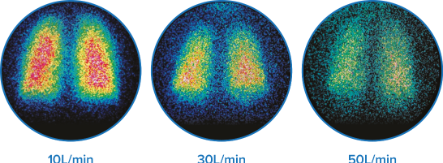

صور تمثيلية للترسب الرئوي عبر معدلات تدفق مختلفة عند 10 و 30 و 50 لتر / دقيقة لدى البالغين الأصحاء.† 6

- توصيل العقار إلى الرئتين بنسبة 3.5% –17%، اعتمادًا على معدلات التدفق †6

- استجابة فعالة لموسعات الشعب الهوائية، حتى مع تدفق الغاز بمعدل 50 لتر / دقيقة‡10